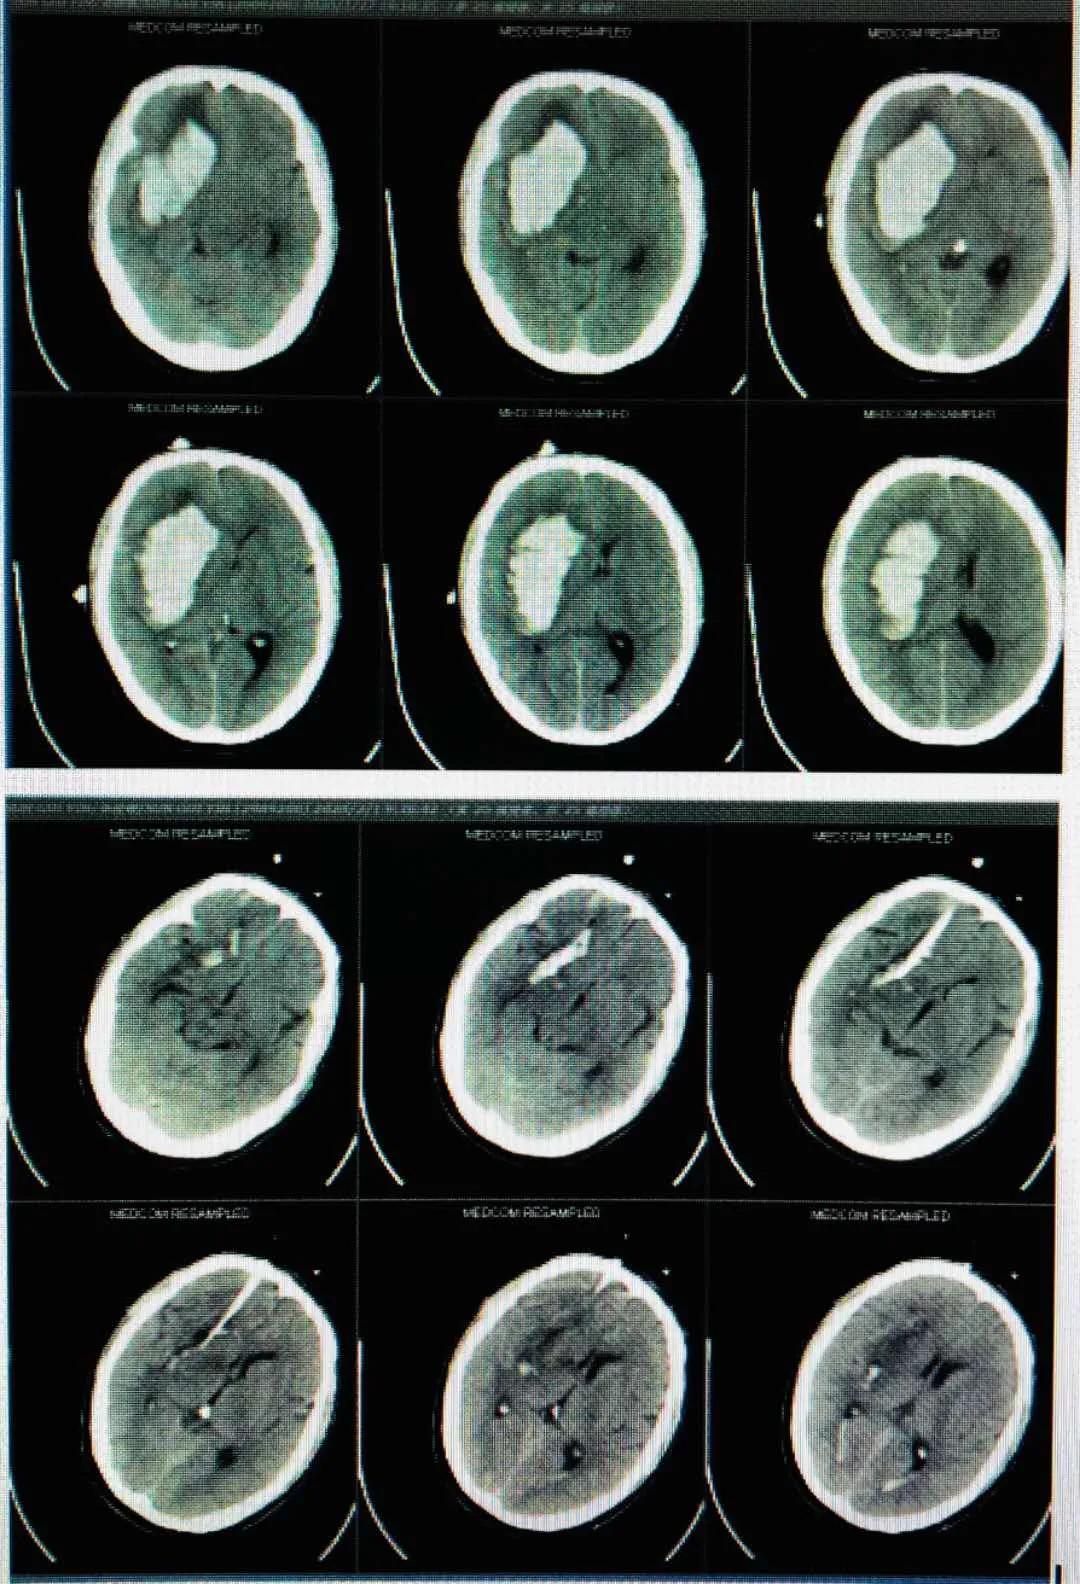

脑室腹腔分流术

患者高某,男性,73岁,于入院2个半月前因外伤致伤头部,当即人事不省,无口吐白沫、双眼上吊、四肢抽搐,无大、小便*禁失**等不适,经福建医科大学附属第一医院治疗后好转。1个月前就诊我院康复科,行康复治疗。半个月前患者开始出现精神状态欠佳,呈痴呆状,意识障碍,大、小便*禁失**。诊断为创伤性脑积水、左侧额部硬膜下积液、右侧颞叶软化灶、两肺下叶炎症。5月18日在局部麻醉下行“脑室腹腔分流术”。

术后,给予预防感染和抗癫痫等对症支持处理,患者病情慢慢恢复。

脑出血脑室引流术

此外,永春县医院还成功开展了“脑出血脑室引流术”。